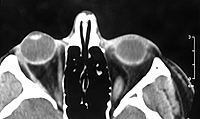

Old examples from film

These are some now obsolete examples of axial images which were scanned from film using either a video digitizer or a flatbed scanner with a transparency adapter.

CT3